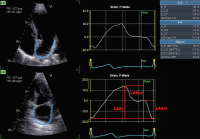

Echo

Abbildung 10: Analyse des linksatrialen Strains aus einem apikalen 4-Kammer-Blick (links oben) und einem apikalen 2-Kammer-Blick (links unten). Man beachte die schmale ROI, die dem dünnen atrialen Myokard angepasst ist. In den beiden mittleren Diagrammen sind die linksatrialen Strainkurven mit Annotierung der P-Welle im Oberflächen-EKG abgebildet (P-P-Gating). Die Messwerte in der Tabelle rechtsseitig geben den Reservoir-, Conduit- und Contraction-Strain des linken Vorhofes im 4-Kammer- und 2-Kammer-Blick sowie biplan gemittelt an. LASr: linksatrialer Reservoir-Strain, LAScd: linksatrialer Conduit-Strain, LASct: linksatrialer Contraction-Strain

Keywords: EchoKardiologiestrain